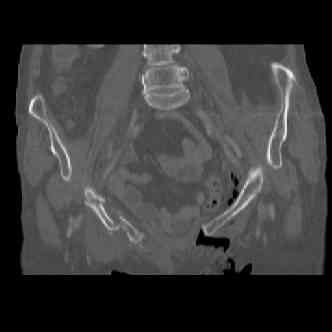

attached are images of a 70 year old female after peds versus car. her own car ran her over.

injuries are limited to the pelvis. left rami open and visible in a 10cm vertical laceration just lateral to left labia majora. wound is grossly clean. no vaginal and no urinary issues. CT scan shows widening of both SI joints anteriorly but I think this is vertically stable pattern.

pt treated that night with I/D and supra-acetabular frame to close the ring. consideration was given for SI screws bilateraly, but given time of night and other factors decision made not to proceed.

so the question is what next operatively if anything? concerns are infection, nonunion anteriorly and possible incompetence of the pelvic floor which may lead to prolapse issues. right rami are comminuted and plating may entail ilioinguinal approach to extend plate laterally to right iliac wing. retrograde screw up right rami is an option but I am not convinced it will add much. adding SI screws very doable, but major concern is restoring anterior ring. so far wound is clean and closed over a drain, and I have no plans to open it back up and wash again.

attached are several CT cuts. please let me know if you need more. the CT is pre-pelvic ex-fix placement.

Thank you.

I wouldn't plate the front.

But I would add screws posteriorly.